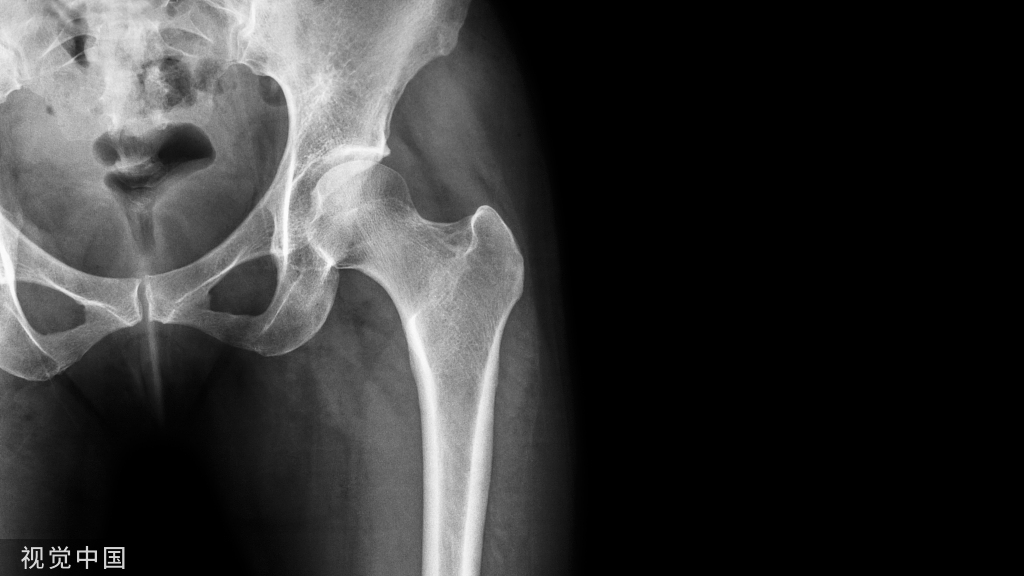

胫骨远端骨折的Poller钉置入方法

股骨远端骨折的Poller钉置入方法。二、改良Poller钉技术